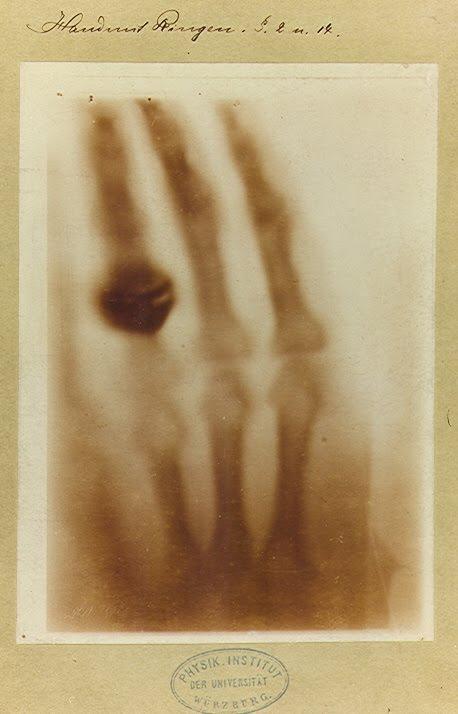

Pasó algún tiempo reproduciendo estas capacidades para lo que se valió de diferentes objetos, hasta que el día 22 de diciembre -de aquél mismo año- decidiese hacer la primera prueba con humanos y le pidiera a su esposa Anna Bertha que apoyase la mano sobre la placa. El resultado fue sorprendente: en la primera radiogradía de la historia podían verse los distintos huesos de la mano izquierda y en uno de los dedos, como flotando, su alianza matrimonial.

El 28 de diciembre Röntgen dió a conocer a la comunidad científica su descubrimiento, los que él mismo denominó Rayos X y por los que nunca quiso, a pesar de no ser hombre de holgada economía, cobrar derecho ni premio alguno. Por su enorme utilidad, aunque también por este motivo, los Rayos X no tardaron en ser conocidos en todos los rincones del mundo.